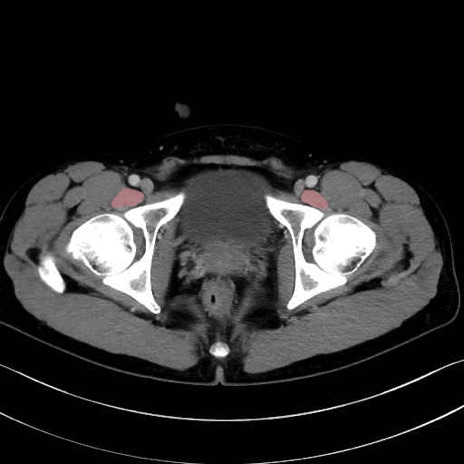

4. 深層外旋六筋(股関節の深部)

梨状筋 (Piriformis)

内閉鎖筋 (Obturator internus)